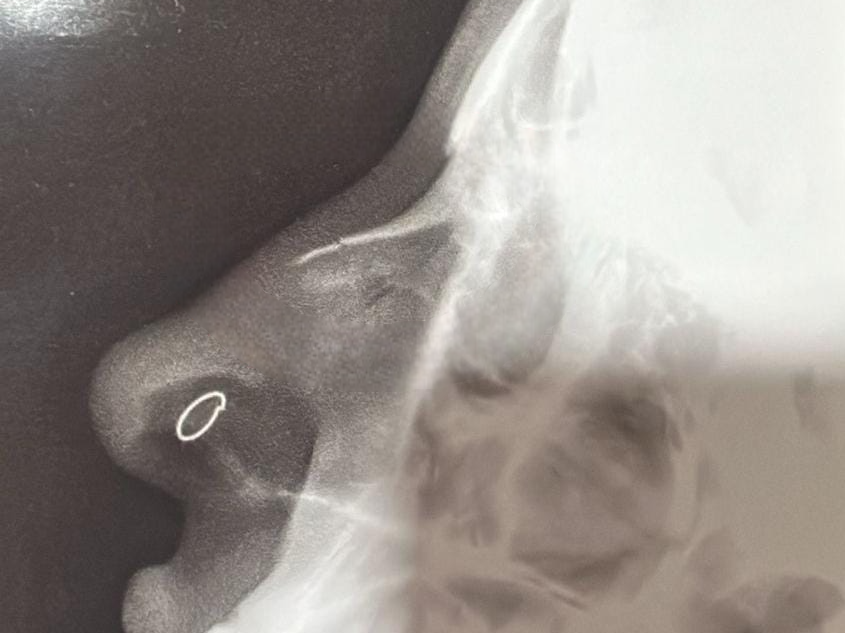

Vítima apresentou à polícia radiografia que aponta fratura no nariz (Imagem: Divulgação)

Após a agressão, a mulher procurou atendimento médico em um pronto-socorro particular na região central da cidade e, posteriormente, compareceu ao plantão policial, onde formalizou a denúncia. Uma cópia da radiografia, que aponta fratura, foi anexada à queixa.